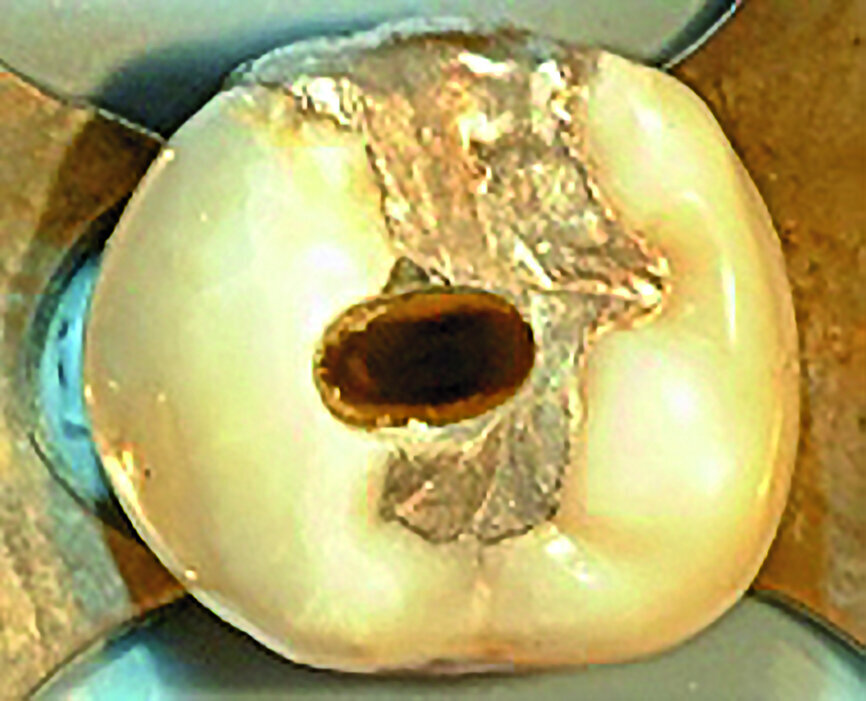

Figs. 4a et b : Cavités d’accès réalisées dans une molaire préparée pour une couronne et requérant un traitement canalaire (à gauche). Radiographie postopératoire (à droite) montrant le résultat admirable de la mise en forme du canal radiculaire, du nettoyage et de l’obturation – malgré la dimension minimale de l’orifice d’accès. À noter le plafond de la cavité pulpaire qui subsiste largement. (Photos : fournies par le Dr Steve Baerg)